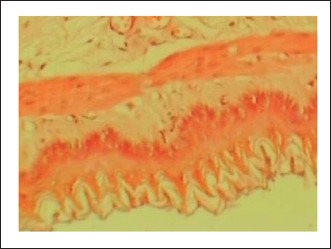

Results: The study found that the extract effectively protected against indomethacin-induced gastric mucosal injuries. It showed a significant (p < 0.05) reduced the severity of lesions and increased the percentage protection of ulcers. The extract also decreased gastric acidity and increased mucus production, indicating its cytoprotective properties. Histopathological examination revealed that the extract prevented morphological changes such as inflammation, necrosis, and ulcers caused by indomethacin. Statistical analysis was performed to determine significant differences between groups.